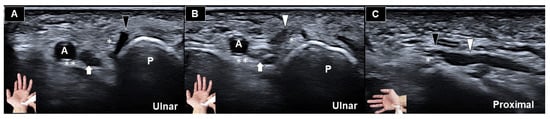

Ultrasonograhic Identification of the Entrapment of a Transligamentous Sensory Branch of the Ulnar Nerve

by Wei-Ting Wu, Ke-Vin Chang and Levent Özçakar

Diagnostics 2026, 16(3), 405; https://doi.org/10.3390/diagnostics16030405 - 27 Jan 2026

Abstract

Anatomical variations of the ulnar nerve at the wrist are uncommon and may lead to diagnostic confusion or iatrogenic injury if unrecognized. We present an ultrasound-based identification of a rare transligamentous ulnar nerve sensory branch entrapment in an elderly male with chronic ulnar-sided [...] Read more.

Anatomical variations of the ulnar nerve at the wrist are uncommon and may lead to diagnostic confusion or iatrogenic injury if unrecognized. We present an ultrasound-based identification of a rare transligamentous ulnar nerve sensory branch entrapment in an elderly male with chronic ulnar-sided hand paresthesia. High-resolution ultrasonography revealed an aberrant sensory branch deviating from the ulnar nerve, piercing the palmar carpal ligament, and coursing superficially rather than entering Guyon’s canal. Further assessment demonstrated focal nerve flattening within the ligament with proximal enlargement, consistent with entrapment. This case highlights the value of ultrasound in detecting rare peripheral nerve variants and their entrapments. Therefore, it is also noteworthy to extend the sonographic evaluation beyond conventional entrapment sites at the wrist. Full article

(This article belongs to the Section Medical Imaging and Theranostics)

Show Figures

Figure 1